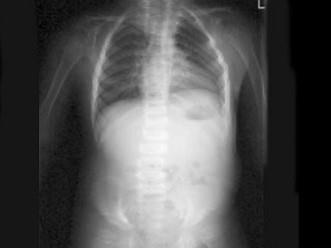

问题 女,3岁,身高不增,智力正常,请结合图像,选出最可能的诊断 ( )

选项 A、粘多糖贮积症I型 B、MPSII型 C、肾性骨病 D、粘多糖贮积症IV型 E、维生素D缺乏症

答案 D